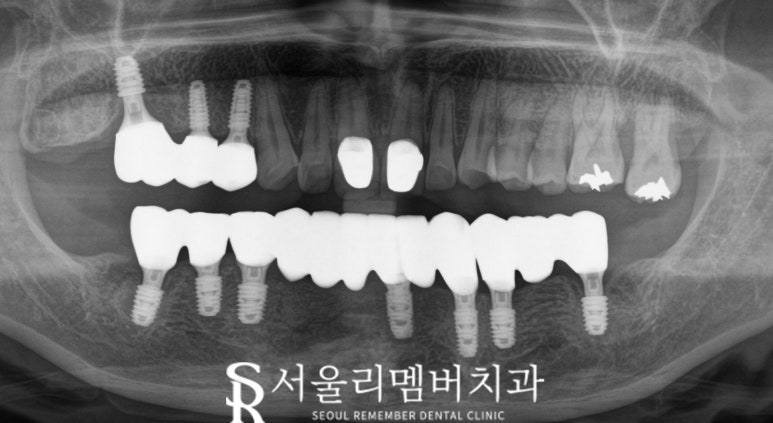

- 치료 과정: Implant 식립

사진과 같이 하악의 모든 치아를 발치한 후,

Implant를 심고 보철을 올려드렸습니다.

서울대입구 치과 에서 진행하는 임플란트 는

대학병원급 전문 장비를 이용한

디지털 진료로 진행했는데요,

이를 통해 더욱 무탈하고 정확하게 심을 수 있었습니다.

특히 CT와 3D 스캐너를 사용해

구강 구조를 정확히 분석한 후

계획대로 알맞게 심었습니다.

이러한 장비 덕분에

chair time도 단축시킬 수 있었습니다.

위턱 오른쪽 어금니도 발치 후 식립하는

과정이 계획대로 정확히 이루어졌습니다.